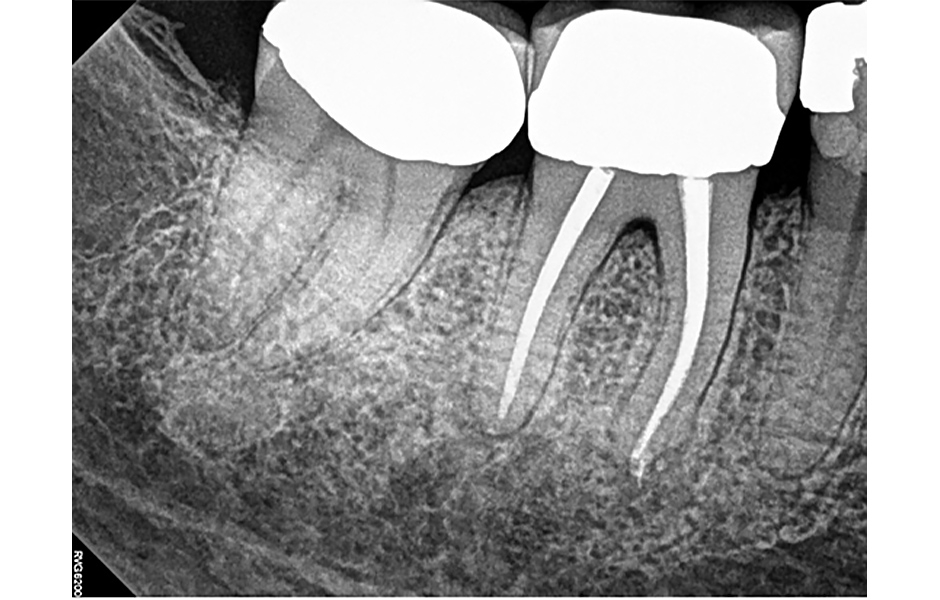

Kontrola po 12 měsících v červnu 2023: Pacientka byla asymptomatická a sondážní hloubky kolem zubu 46 byly < 4 mm. Zub 46 byl bez citlivosti na poklep a palpaci, s fyziologickou mobilitou. Pacientka souhlasila s pořízením PA rentgenových snímků (obr. 6 a, b) a CBCT skenu s omezeným zorným polem (obr. 7 a–c). PA snímky vykazují známky hojení v oblasti meziálních i distálních apexů.

CBCT sken (obr. 7a) ukazuje zaplnění středního meziálního kanálku a konvergenci distobukálního (DB) a distolingválního (DL) kanálku. Koronální řezy meziálního a distálního kořene (obr. 7 b–c) potvrzují apikální hojení obou kořenů. Klinické a radiografické nálezy indikují, že zub 46 je zhojen. Další kontrola není nutná, pokud pacientka nebo její zubní lékař nezaznamenají změny v klinických či radiografických příznacích.

Obr. 6a, b: Kontrolní PA rentgenové snímky zubu 46 v červnu roku 2023.

Obr. 7a–c: Kontrolní CBCT řezy zubu 46 – a) axiální, b) meziální kořen, c) distální kořen.